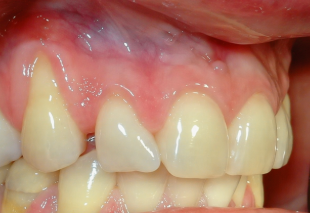

Рецессия десны

Рецессия десны - когда уходит защита

Рецессия - это состояние, при котором десна постепенно смещается, открывая корень зуба. Сам зуб при этом может оставаться абсолютно целым, но меняется его внешний вид: он становится визуально длиннее, а зона у десны - более чувствительной.

Важно понимать, что десна - это не просто «контур», который формирует улыбку. Это защитный барьер. Она закрывает корень зуба, который по своей структуре намного уязвимее эмали. Когда десна уходит, эта защита теряется и именно тогда появляются реакции на холодное, кислое или даже на обычную чистку зубов.

Причины рецессии могут быть разными: от особенностей тканей и анатомии до нагрузки, травмы или воспаления. Но суть остаётся одной - это процесс, связанный с мягкими тканями.